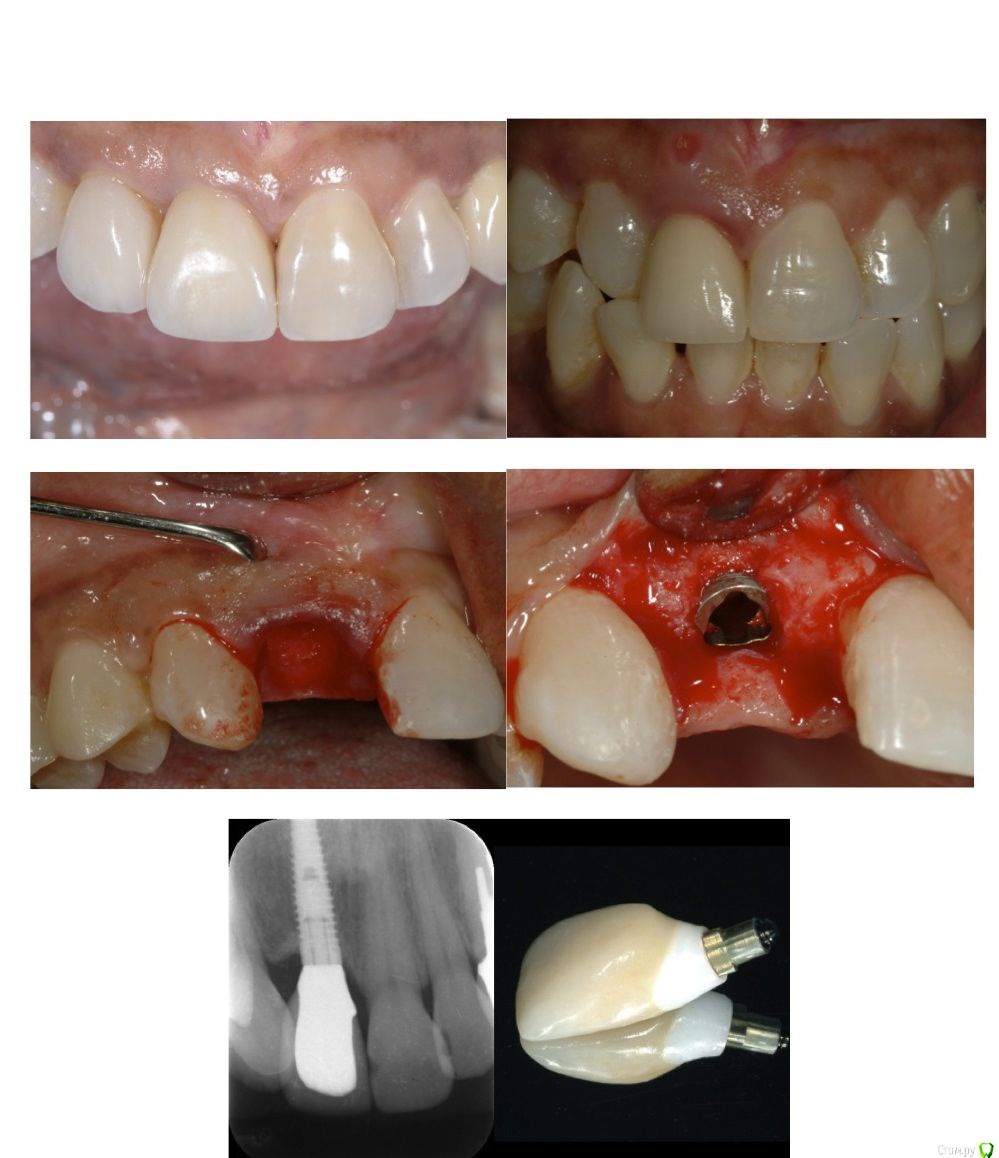

День 2: Импланты в эстетической зоне:

Немедленная или отложенная имплантация

Атравматичное удаление

Стратегии выбора временных конструкций при немедленной или отложенной имплантации

Винтовая или цементная фиксация

Современные концепции биологических абатментов

Обзор современных материалов для финальных коронок: достоинства и недостатки

Дизайн импланта для немедленной установки после удаления

Как достичь стабильного мукозального барьера

Роль вестибулярной костной пластинки и периодонтальной связки

Факторы ремоделирования тканей: обзор клинических примеров

"Улыбка - это уникальная подпись каждого человека", - повторяет Бернар Туати в своих международных докладах и ежедневной практике, делясь с коллегами секретами своего успеха. Двухдневный курс посвящен воссозданию естественной гармонии как на зубах, так и на имплантах.